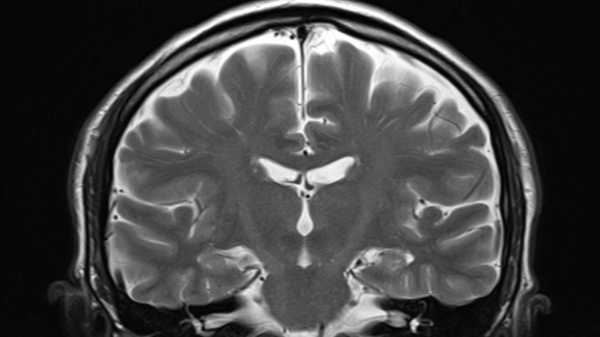

A recent study details how a model based on machine learning employs MRIs to forecast the tempo at which an individual ages, plus, in sequence, their odds of developing illnesses tied to aging.(Image credit: Rajaaisya/Science Photo Library via Getty Images)ShareShare by:

In order to create their resource, the group scrutinized the brain MRIs extracted from this population at age 45, then subjected the data concerning the composition of their brains — the expanse and density of different cerebral regions and the proportion of white to gray matter — via a machine learning algorithm.